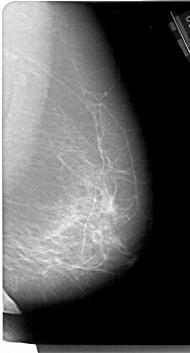

A_1190_1.RIGHT_MLO

RIGHT_CC LINES 6526 PIXELS_PER_LINE 3271 BITS_PER_PIXEL 12 RESOLUTION 43.5 NON_OVERLAY

RIGHT_MLO LINES 6706 PIXELS_PER_LINE 3601 BITS_PER_PIXEL 12 RESOLUTION 43.5 NON_OVERLAY